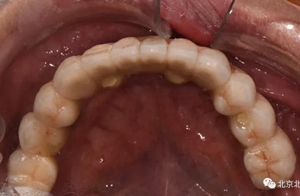

圖十九:永久修復(fù)完成

圖二十:永久修復(fù)咬合關(guān)系

圖二十五:口內(nèi)照。